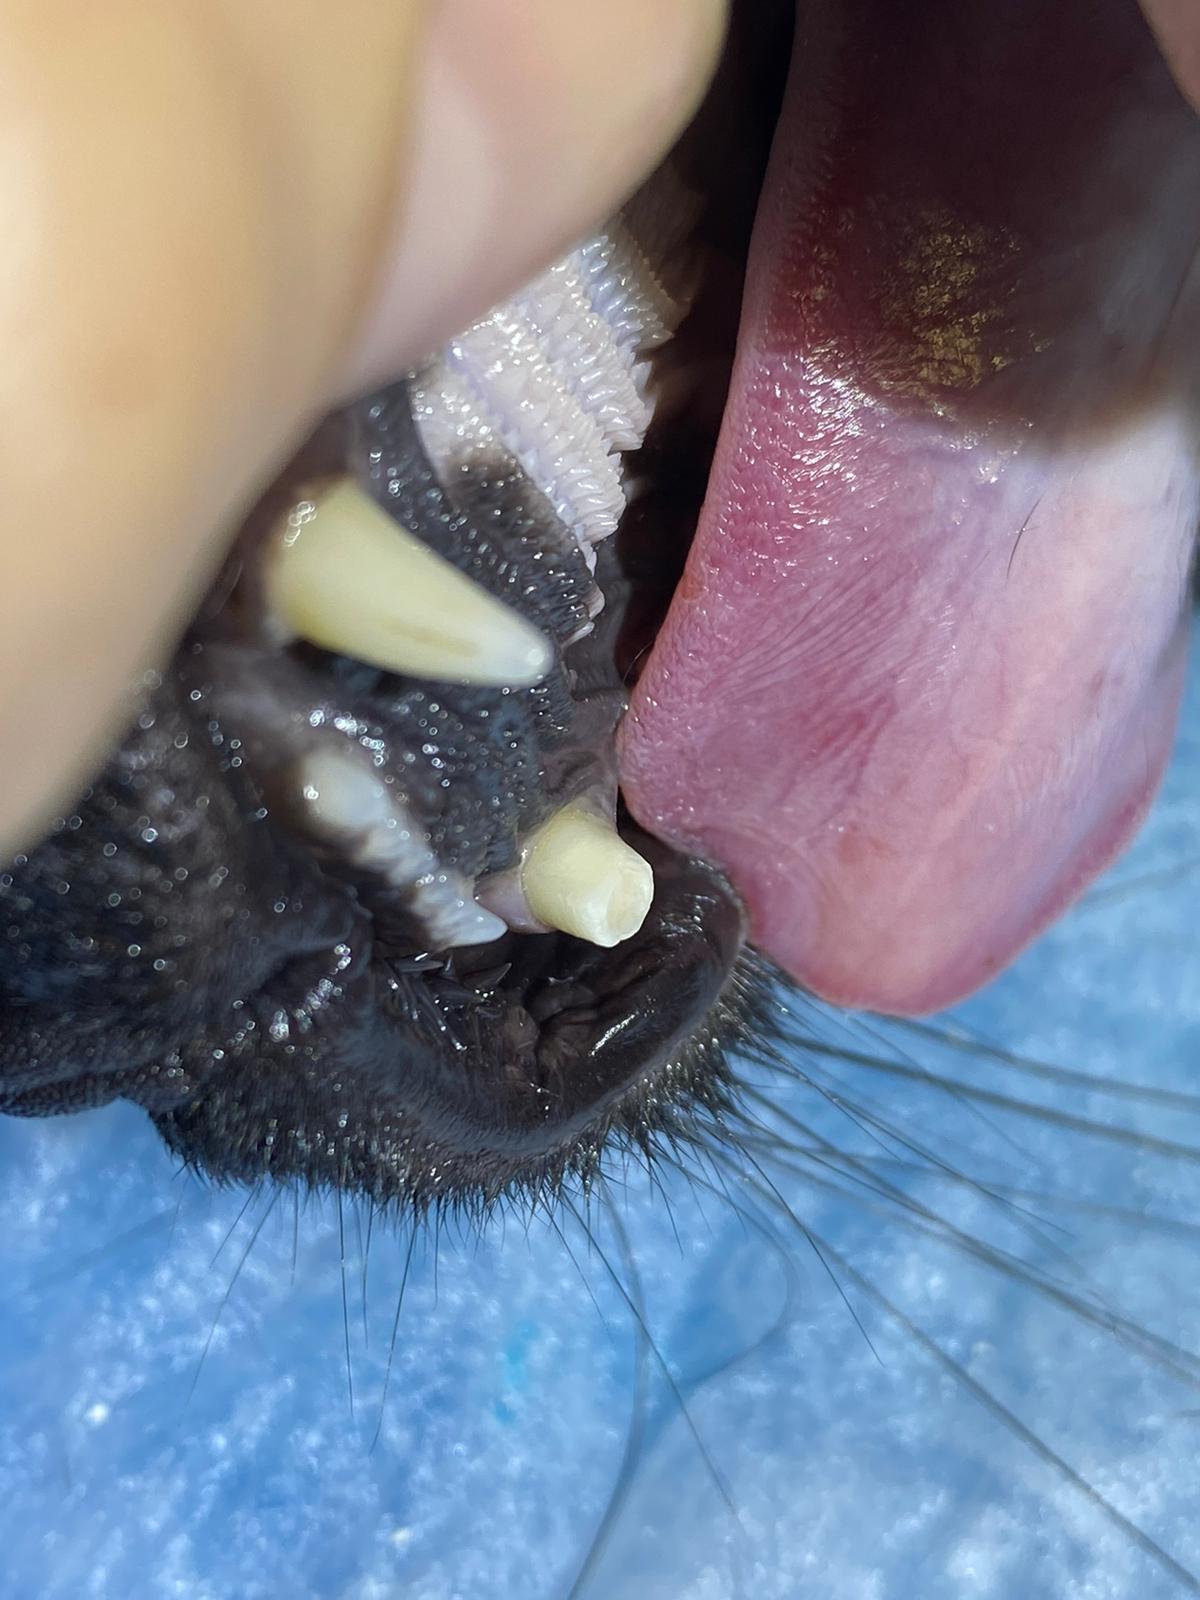

Vitální amputace pulpy (VPT - vital pulp therapy) se provádí převážně u psů mladších 18 měsíců. Cílem téhle léčby je zachovat strukturu zubu a umožnit mu dozrát. Je to alternativa k extrakci nebo terapii kořenových kanálků. Pomocí sterilních nástrojů se odstraní malé množství dřeňové tkáně. Následně se na nově obnaženou dřeň aplikuje léčivá vložka (kalciumhydroxid), která umožní hojení a vytvoření přirozeného dentinového můstku a tým uzávěr dřeňové dutiny.

Zvláště u mladých zubů (do 18 měsíců) je zub velice křehký a snadno se může zlomit, navíc nedošlo k dokončení vývoje kořene. Pokud by byl takový zub ošetřen terapií kořenových kanálků, zůstal by trvale křehký a nevyvinutý, tj. snadno by se mohl zlomit. Naopak, terapie vitální amputace pulpy umožní zubu dokončit vývoj kořene, jeho uzávěr a také nabýt na síle a stát se odolnějším vůči zlomení.

Trauma zubů je u společenských zvířat bohužel běžná a je často důsledkem nevhodných žvýkacích hraček nebo agresivního chování při žvýkání a hraní. V mnoha případech má zlomený zub obnaženou dřeň. Pokud je trauma čerstvé (trvá méně než 48 hodin), lze zvolit terapii vitální amputace pulpy, aby zub zůstal živý. To je zvláště důležité u mladých zvířat, která mohou mít zuby s nedokončeným vývojem kořene (hrot kořene ještě není uzavřen). V případě téměř expozice dřeň není aktivně vystavena vnějšímu prostředí. Na dřeni je sice stále velmi tenká vrstva dentinu, ale zde existuje vysoké riziko nevratné pulpitidy (pro zvíře bolestivý stav). Třetí možností využití terapie vitální amputace pulpy je v případech liguovezních mandibulárních špičáku (spodné špičáky jsou vyhnuté směrem dovnitř k jazyku) jako ortodontická procedura. Takhle rotované spodní špičáky následně zraňují tvrdé patro zvířete a můžou následně způsobit oronazální píštěl. Oronazální píštěl je abnormální komunikace mezi dutinou ústní a nosní, která vede k chronickým infekcím horních cest dýchacích. Provedením redukce korunky a terapie vitální amputace pulpy na dolních špičácích je dosaženo bezbolestné okluze bez ztráty těchto funkčně důležitých zubů.